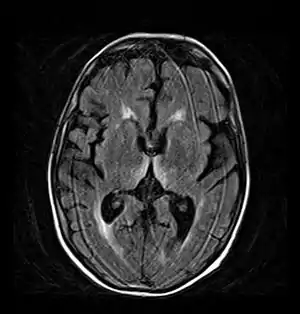

A síndrome de Korsakoff é atribuída a uma lesão no diencéfalo, especificamente no núcleo dorsomedial do tálamo e nos corpos mamilares, que, como vistos, são essenciais na construção da memória, o que causaria a amnésia anterógrada. Para agravar esse quadro ocorre também atrofia cortical generalizada, afetando especialmente o lobo frontal e temporal. Essa lesão no córtex cerebral seria a responsável pela amnésia retrógrada e até mesmo uma complicação à já existente questão da identidade, sendo que o lobo frontal tem enorme importância na formação da personalidade e na integração de inúmeras informações corticais.[2]

Diagnóstico

O exame do sistema nervoso e muscular pode mostrar muitos danos[3]: